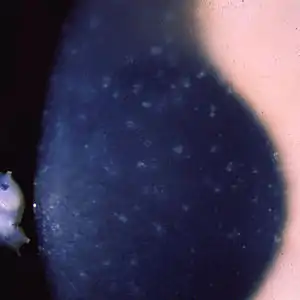

| Multiple opaque spots in the corneal epithelium | |